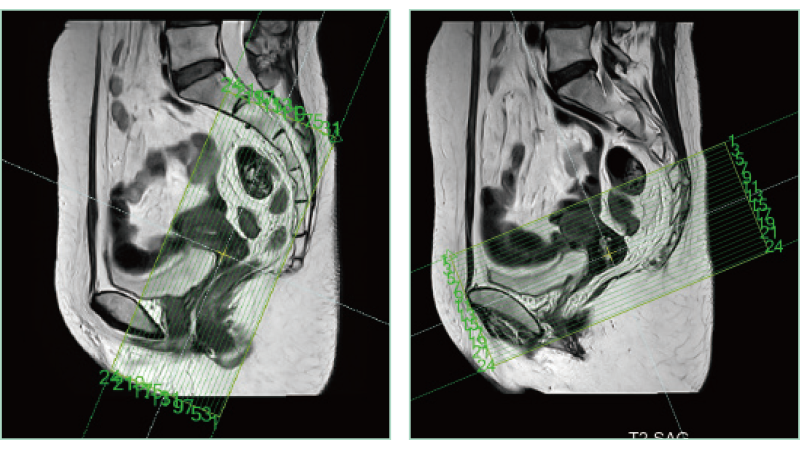

AutoPose FemalePelvis

AutoPose Knee

スライスライン設定サポート機能"AutoPose"は、Scanogram撮像終了と同時にスライスラインを設定します。